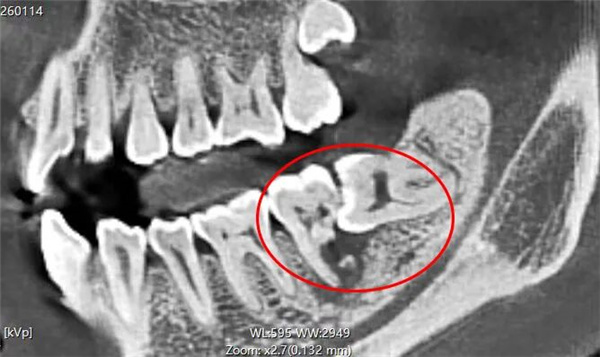

▲术前牙片

接诊的黄泽浩医生为他进行了口腔检查和拍片检查发现:这颗水平阻生的智齿死死抵在邻牙牙根上,长期的压迫导致邻牙牙根大面积吸收,牙根被“顶”出一个大洞、牙槽骨流失。最终邻牙也无法保留,只能与智齿一同拔除。